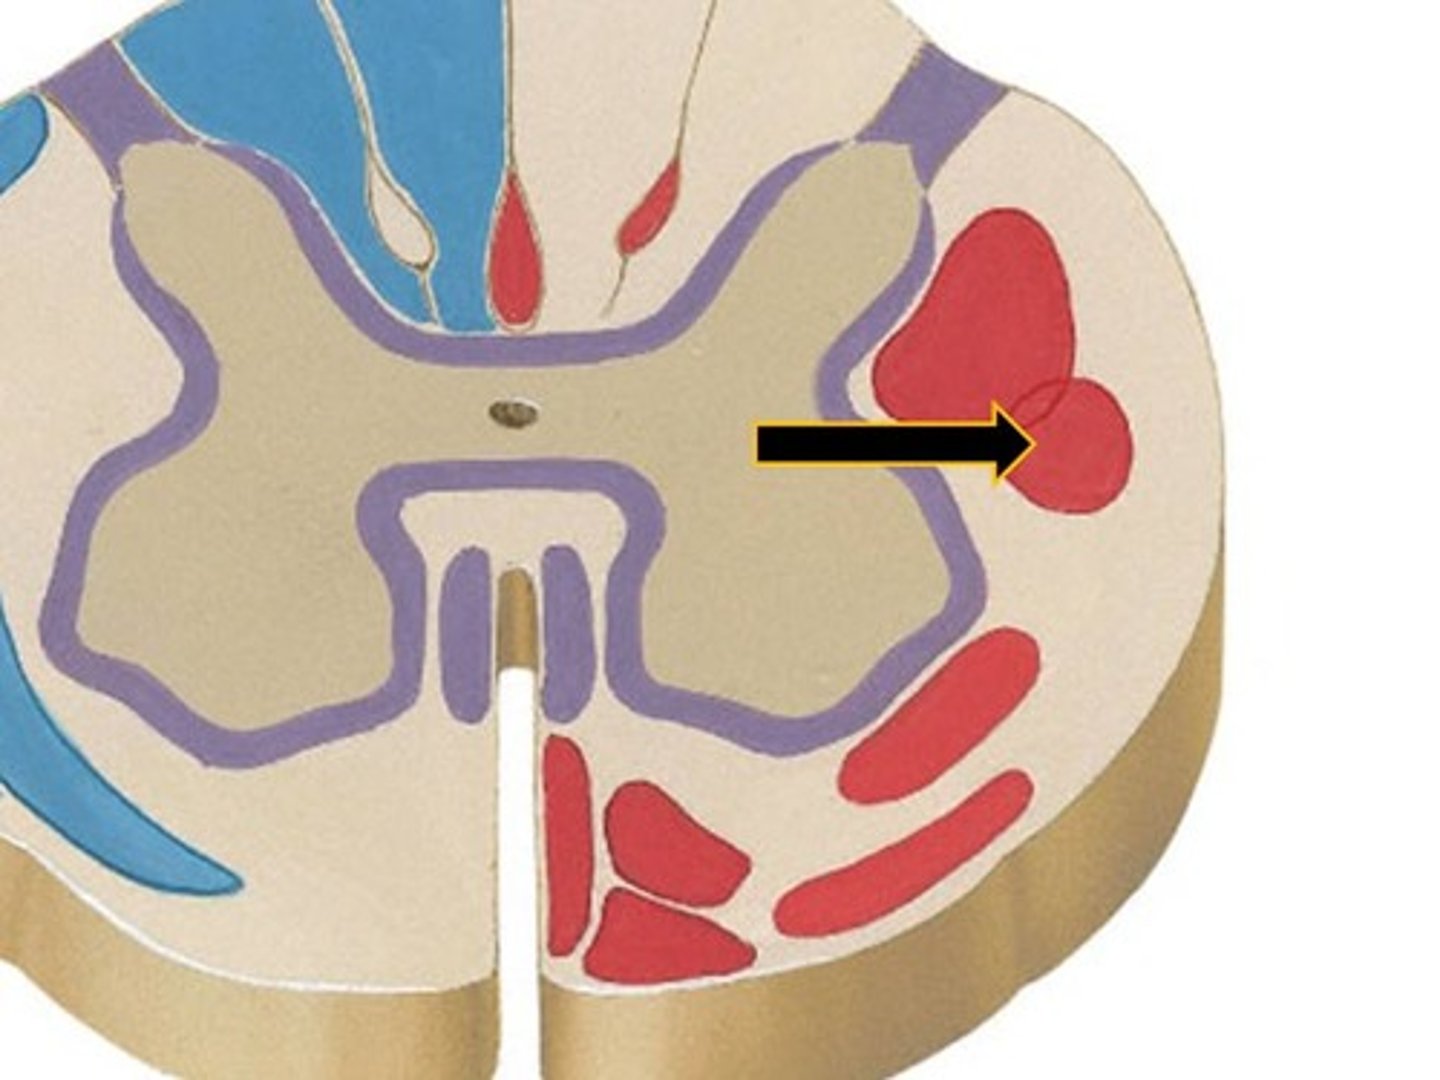

Spinal cross section (1)

Spinal cross section (2)

dorsal horn of spinal cord

cell bodies synapsed by afferent neurons (sensory)

ventral horn of spinal cord

The upper motor neurons that control the skeletal muscles are found in

lateral horn of spinal cord

Contains the cell bodies of the preganglionic ANS neurons

dorsal column

a white matter tract on the dorsal side of the spinal cord, carrying fine touch and proprioceptive axons to the brain stem

spinothalamic tract

pain and temperature

corticospinal tract

What tract is responsible for voluntary refined movements of distal extremities?

dorsal rootlets

ventral rootlets

spinal nerves

central canal of spinal cord

ventral white comissure

Dorsal Root Ganglion (DRG)

associated with the dorsal horns; cell bodies of sensory neurons are located here